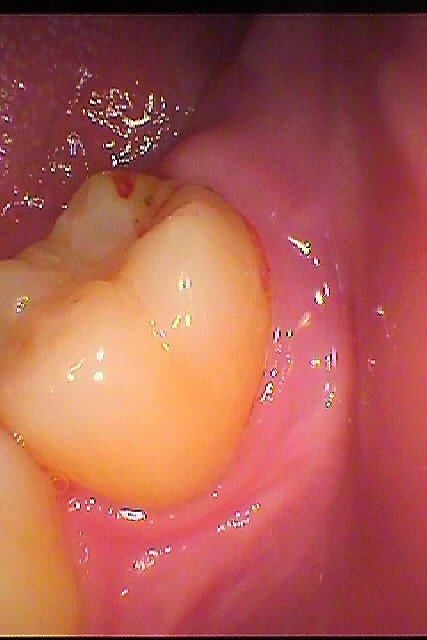

左下親知らずの抜歯 埋伏歯の抜歯|お知らせ |広島市安佐南区の歯科医院 左下親知らずの抜歯 埋伏歯の抜歯 トップ お知らせ・ブログ お知らせ 左下親知らずの抜歯 埋伏歯の抜歯 左下親知らずの抜歯 埋伏歯の抜歯 ここに埋まっている親知らずが腫れるとのこと 埋まっている親知らずを抜歯していきます こんな感じで埋まっています 麻酔をかけて開けていきます 動かないので分割してみます このように抜歯しました 縫合して終了となります腫れるかもしれません 腫れるかもしれません Web診療予約 初めての方へ 選ばれ続ける理由 院内設備について 歯が痛いしみる一般歯科 歯がぐらぐらする歯周病 健康な歯を保ちたい予防歯科 子供の虫歯予防をしたい小児歯科 銀歯をセラミックに審美歯科 白い歯を目指しませんか?ホワイトニング 矯正専門医がいるので安心矯正歯科 抜けた歯を補いたいインプラント・入れ歯 医院案内 スタッフ紹介 メリィハウス歯科クリニックオフィシャルホームページ ラベンダー歯科クリニックオフィシャルホームページ お知らせ・ブログ ホーム 診療科目 一般歯科 歯周病治療 予防治療 小児歯科 審美治療 ホワイトニング 矯正歯科 入れ歯・インプラント マウスピース矯正 初めての方へ 院長・スタッフ 設備紹介 医院案内・アクセス メニューを閉じる